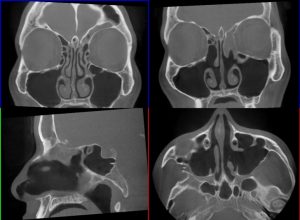

僕自身があまりに痛いというため、脳に異常があるかもしれないということで、MRIを撮ったりCTを撮ったり。

「おでこの周辺に膿が溜まってますね」という診察結果を受けることに。

ここでやっと、この症状が副鼻腔炎であることが判明です。

医者ではないので不確かな部分もありましたが、実際に僕自身の前頭洞がどのような状況になっているのかを、もらったCTで確認しながらまとめました。

実際に大学病院で診察してもらった結果をもとにしたものなので、適当なものではありません。

大学病院で再度手術をすることになったものの、前頭洞ではなくおでこに骨を空けて通り道を作るという手術になりました。